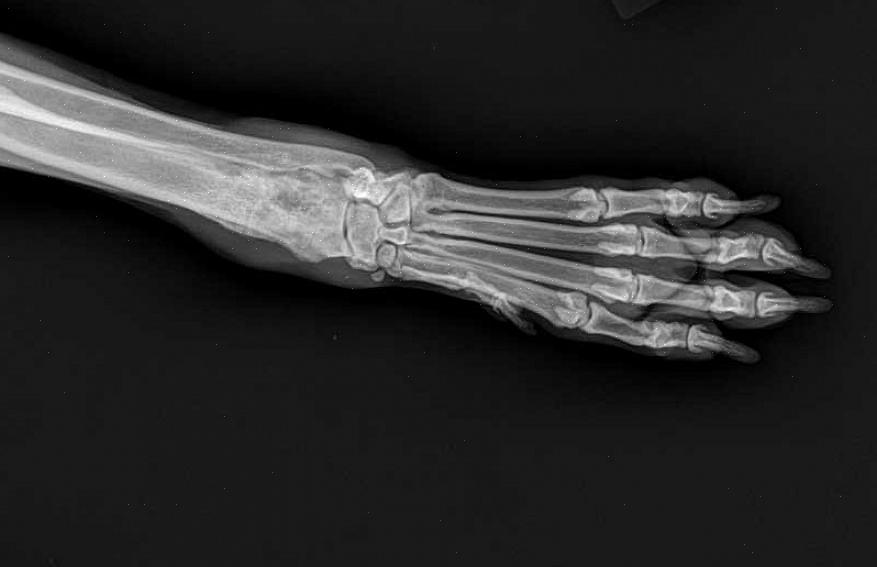

Radiografi

Osteosarkom kan presumptivt diagnostiseres basert på radiografisk bevis. Bensvulster har ofte et flekkete utseende som tydelig kan sees. Imidlertid er en vevsprøve nødvendig for å stille en definitiv diagnose. Din veterinær kan være i stand til å utføre de ekstra testene som trengs. Eller du kan bli henvist til en veterinærspesialist som en ortopedisk kirurg eller onkolog.